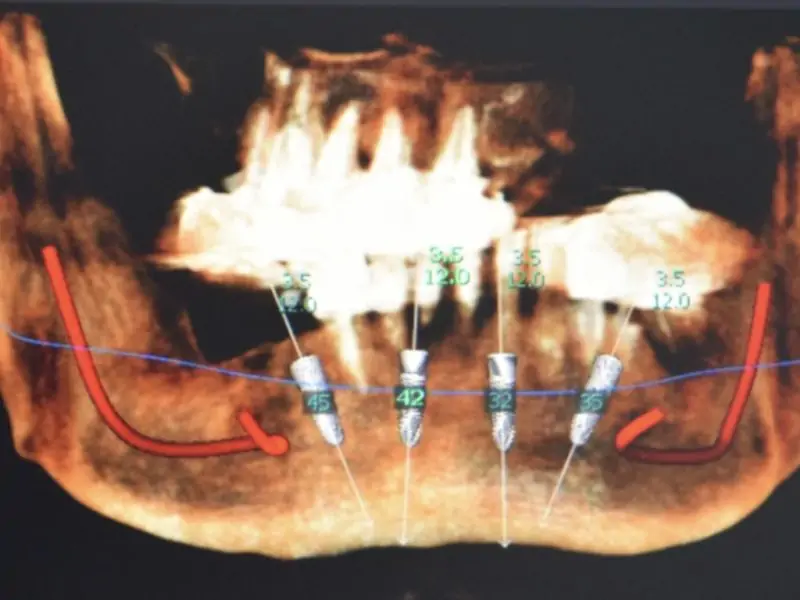

The use of an arch to help praparing the ostheotomy in terms of inclination and positioning can be a great option to easily define the correct positionin for an all on four concept. This patient came with the request of stabilizing his own prosthesis so the treatment plan included the insertion of 4 implants on which we will use the suitable straight and angulated MUA to stabilize a retentive bar to retain a duplicate of the pre-existing prosthesis.

During the surgical session the preparation of the implant sites was made with the help of the guide arch that have to be inserted in the medial area and gives the indication on the correct positioning of implants for an all on four or all on six concept prosthesis. To minimize the tissue trauma we inseted the implants with a flapless surgery and with the use of stops to determine precisely also the lenght of the preparation. Right after the surgery the patient was left with healing screws on top of the implant and with his previous denture which we hollowed internally to avoid trauma on the implants. After 5 months the patient came back we took an impression an made a duplicate of the prosthesis which we used to build the bar to fix on top of MUAs and an internal framework and the retentive caps.

The guide allows to easily determine the inclination of the preparating tools but this also helps also the choice of the angled MUA. During the second session we simpli inserted the Multi unit abutments and fixed the prosthetic bar with the proper screws before trying and checking the occlusion of the definitive prosthesis.